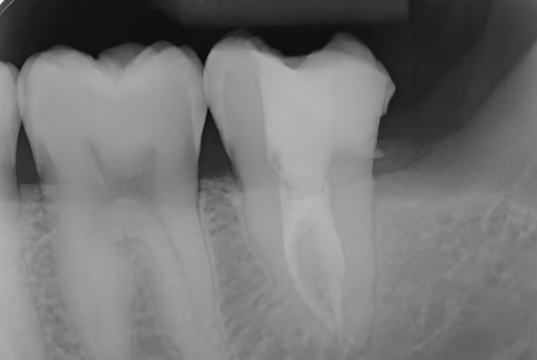

6. Post-Operative

A postoperative periapical radiograph was taken to evaluate the core build-up. The UltraCore dual-cure core build-up dental restorative materials exhibited excellent radiopacity, allowing clear visualization of its margins within the access cavity.

The tooth is now ready for a cuspal-coverage restoration as the next step to restore full function and long-term durability.